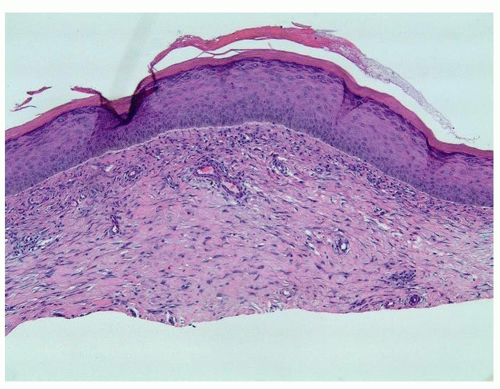

Histopathology

Histologically the composition of keloids is haphazard, thick collagen bundles with extra myofibroblasts and many overactive fibroblasts8 (Figure 8.2.5).